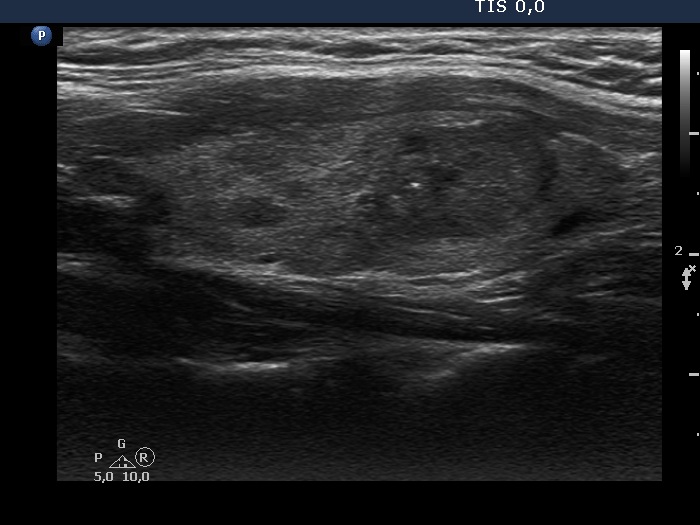

Study on 100 consecutive patients with thyroid nodule - case 021 (ultrasonographic picture 5)

Left lobe, longitudinal scan. It would be hard to interpret the brightest echogenic granule other than a microcalcification.